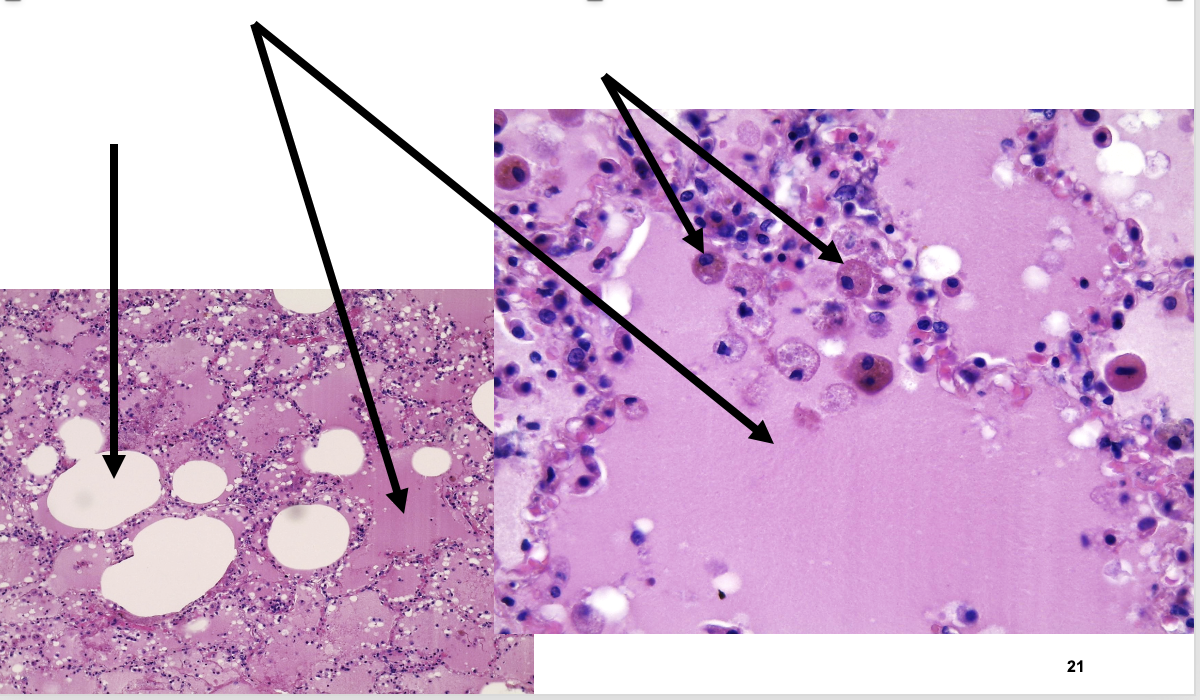

pathologie emfyseem bij rokerslong

vernietiging van alveoli (vergroting luchtruimte en honingraat structuur)

afname alveolaire capillairen

geen/ weinig fibrose

lichte inflammatoire reactie

antracotisch pigment in macrofagen

anthracosis pigment

pathologie schimmel

hyphae (schimmeldraad)

enkel te onderscheiden op PAS kleuring

ontstekingsreactie mogelijk

Hyphae